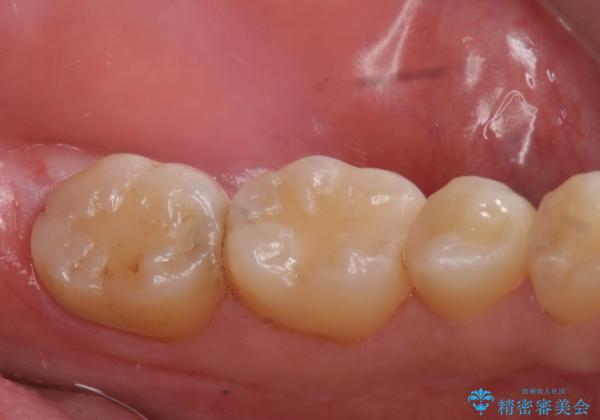

e-maxインレーによる治療

- 定期検診で来院してレントゲンを撮ったところ

歯と歯の間にう蝕ができていました。

拡大鏡下でう蝕を全て除去してe-maxインレーにて治療を行いました。

- e-maxインレー 7.7万円 費用は治療当時の料金となります